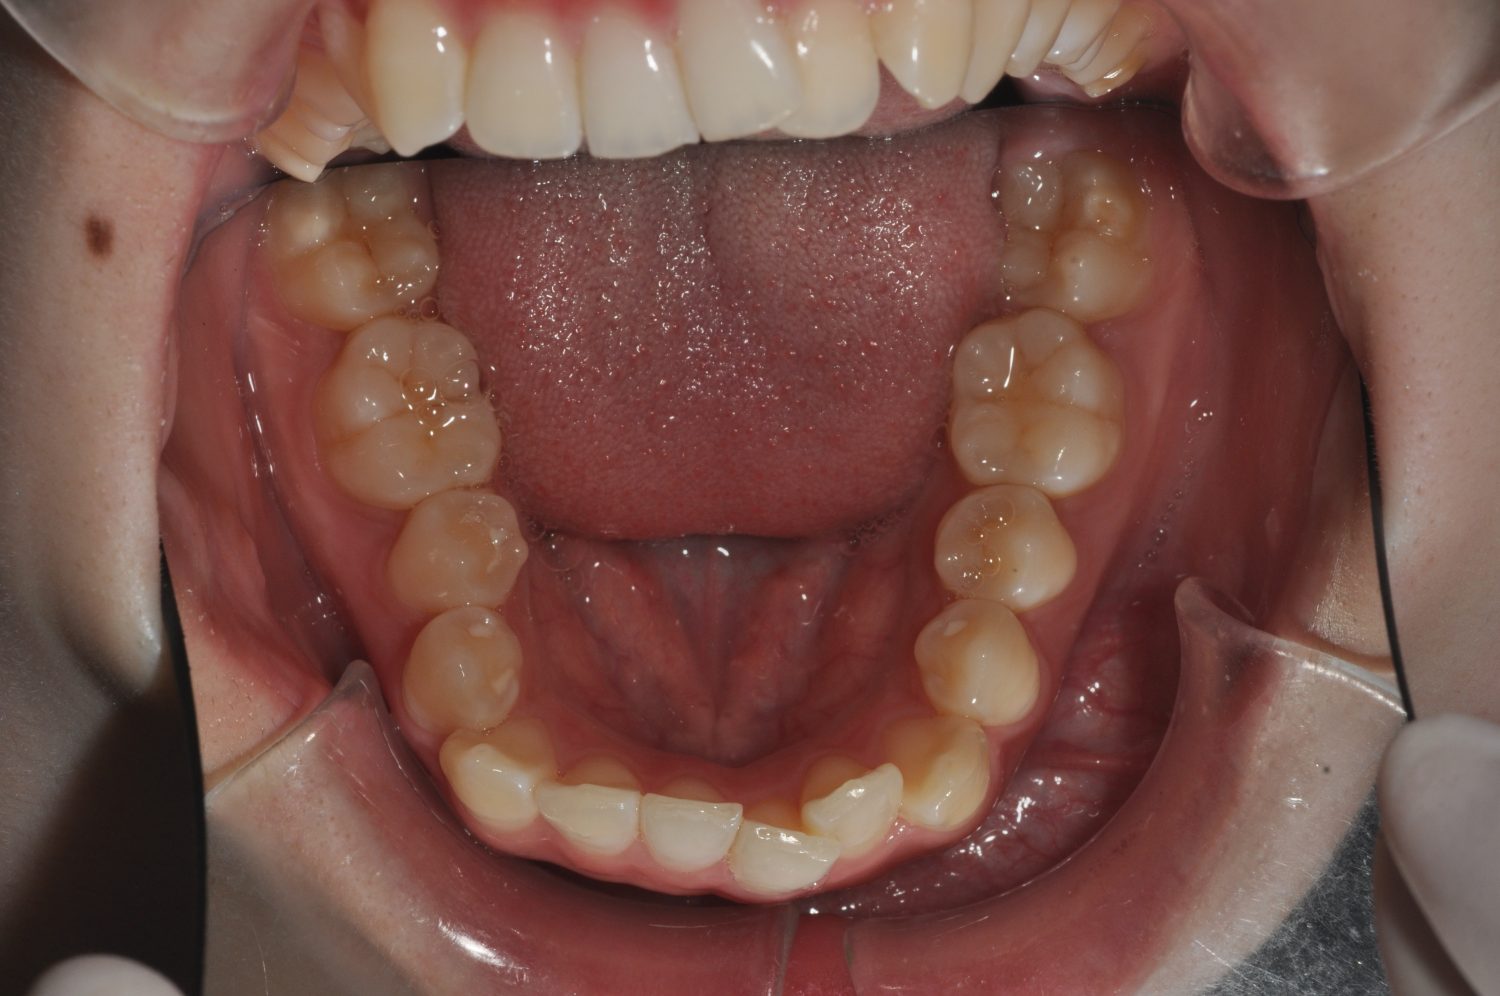

| 主訴 | 前歯部の叢生と正中の不一致 |

| 治療内容 | 軽度の叢生の改善を行うために、非抜歯でのマルチブラケット装置による治療を行った。 |

| 治療期間 | 2年2ヶ月 |

| 想定されたリスク | 矯正後に後戻りする可能性がありました。 |

Ⅰ期治療で叢生、反対咬合の改善をセクショナルアーチとMPAを使用して改善した後、成長観察を行っていました。永久歯の萌出したため、Ⅱ期治療を開始することとなった。上下顎とも骨格的に問題がなかったため、非抜歯で治療を行った。